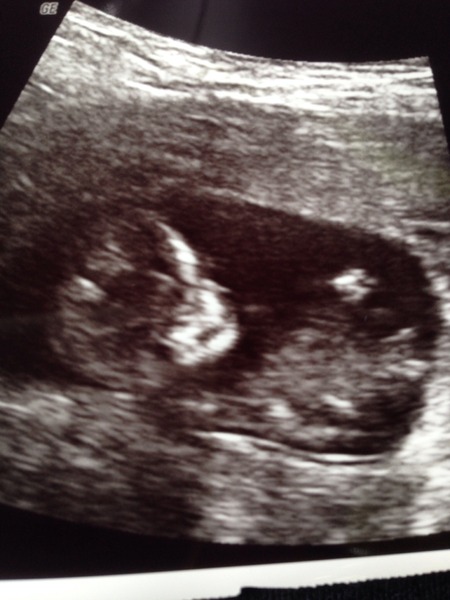

Gillster · 18/06/2015 20:48

So had my private scan and blood test this morning and it turns out that there is a baby in there and I'm not just getting fat! The baby is quite active (clearly takes after DH) and growing slightly ahead of schedule. Nothing from the scan suggests any issues but we'll obviously know more when I get the results back. Here's a pic of the mini Gillster.

Yay to Queazy and Gillster!

What a lovely pic, I'm amazed at how clear they are at this stage!